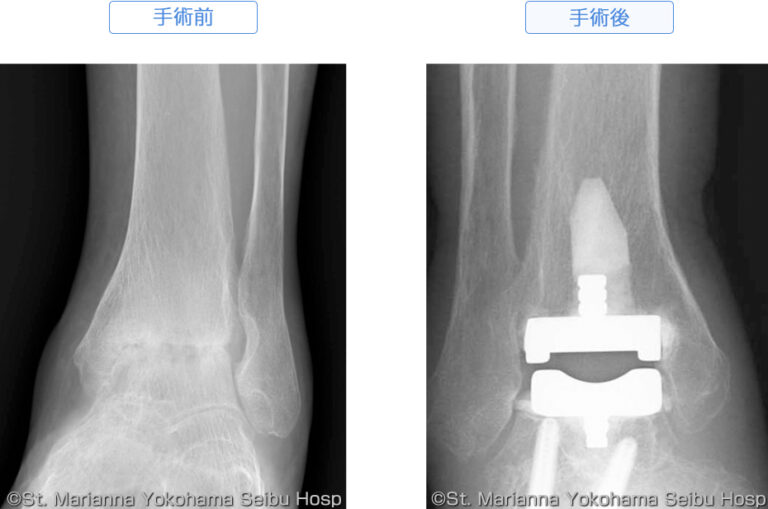

足首置換術は、損傷した足首関節または磨耗した足首関節を新しい関節に置き換えるために推奨される入院手術です。入院手術とは、手術後すぐに帰宅するのではなく、少なくとも1晩は病院で過ごすことを意味します。

足首の関節は脛骨距骨関節として知られています。これは、脛骨(すねの骨) と、脛骨を足の残りの部分に接続する距骨で構成されています。軟骨や骨が定期的に磨耗すると、足首関節に痛みが生じ、歩行困難が生じることがあります。

新しい足首関節は、医療グレードのチタン、クロム、プラスチック部品など、いくつかの異なる材料で作られる可能性があります。

次に、軟骨や骨など、足首関節の損傷した部分を切り取って除去します。損傷した部分が除去されたら、外科医は特殊なセメントを使用して残りの骨に代替の金属関節材料を取り付けます。次に、金属材料と骨の間にプラスチック製のインサートを挿入し、それらが互いにスライドできるようにします。

医師が足首関節の治癒状況を観察できるよう、再診、X 線検査、またはその他の画像検査を受けるために再度来院する必要があります。